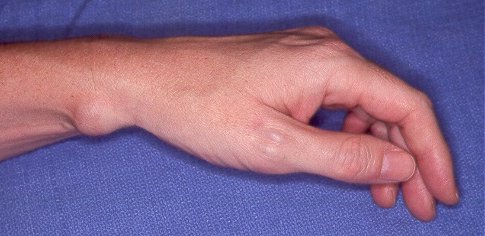

Clinical Example: Volar wrist ganglions

volar wrist ganglion